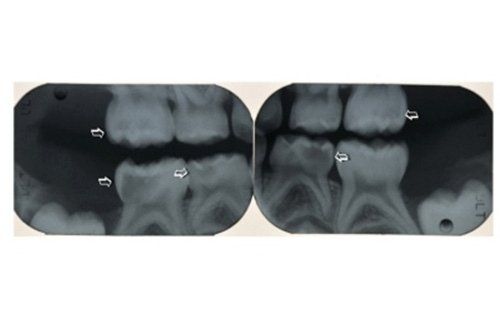

La carie nel bambino è una delle principali cause, insieme all’ortodonzia, di richiesta di intervento del dentista. La patologia ha una evoluzione particolarmente rapida in virtù della scarsità di smalto a difesa del dente da latte. Ciò comporta che, dal momento in cui il dente si ammala a quello in cui ne viene coinvolta la polpa (ovvero il nervo), il tempo sia veramente poco (vedi anche endodonzia pediatrica).

Spesso i dentini da latte cominciano a cariarsi già appena erompono nel cavo orale in quanto sono frequentemente a contatto con zuccheri semplici, come quelli veicolati dal biberon. Particolarmente aggressivi per i denti da latte risultano: tutte le tisane/infusi in commercio in bustine già pronte e pre-zuccherate; il latte zuccherato con qualsivoglia tipologia, incluso il miele; il latte e biscotti, specie nell’uso notturno; l’utilizzo quotidiano, spesso al posto dell’acqua, di succhi di frutta o bevande acide, per citare alcuni fra i più comuni errori commessi nel tentativo di dare una alimentazione completa al bambino, che spesso si traduce nella comparsa di una patologia chiamata